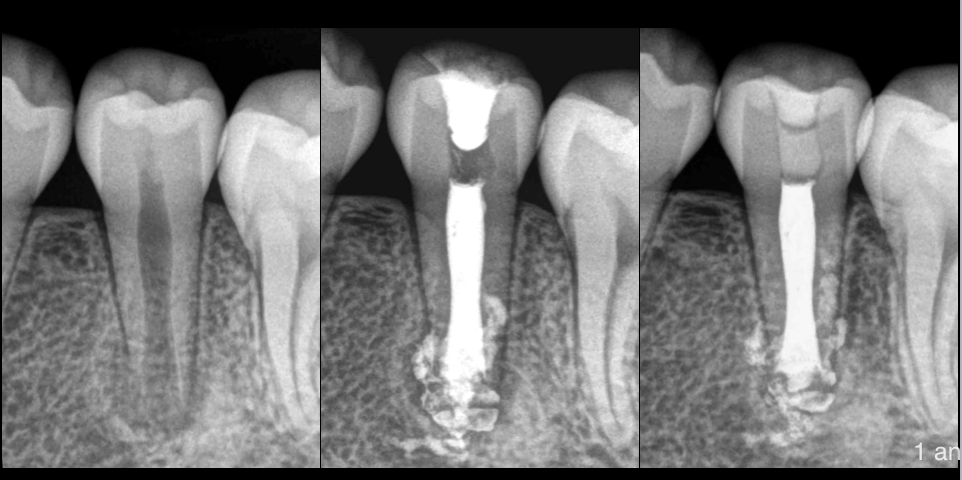

🔍 Patiente de 14 ans

🦷 Pulpe nécrosée, parodontite apicale asymptomatique

🦷 Dent permanente immature